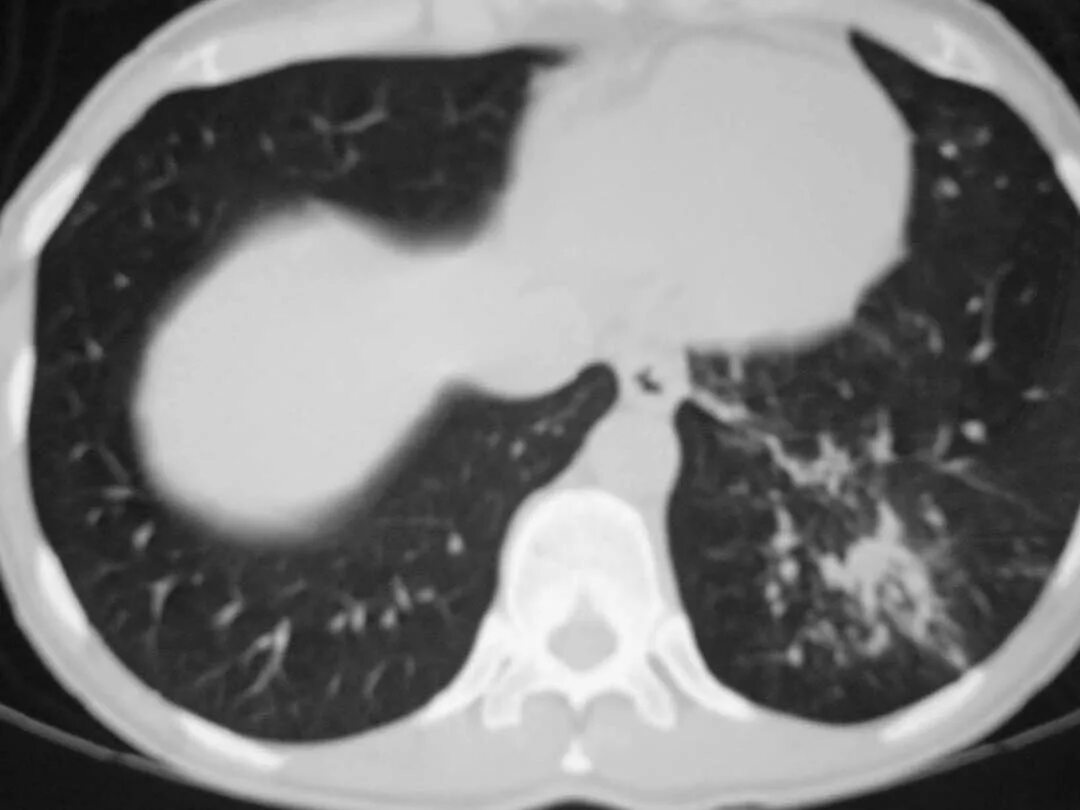

Как выглядит пневмония на кт